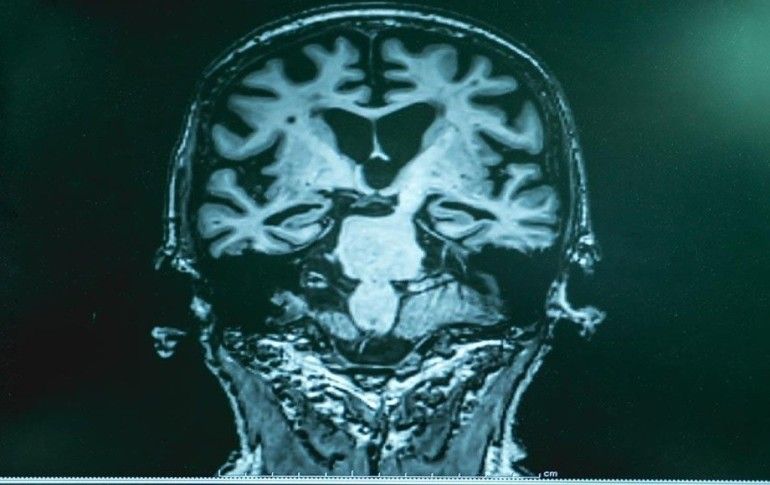

Demans'ın, bellek bozukluklarının tanımı olduğunu dile getiren Medicana Kadıköy Hastanesi Uzm. Dr. Oğuzhan Onultan, "Hastalığın tam olarak adının konulabilmesi için beyin MR’ı, bazı kan tetkikleri, nöropsikolojik muayene ve diğer tetkiklerin yapılması gereklidir. Demans hastalarının yakınları hastalığı konduramadığı için hekimlere geç başvuruyor ve yapılabilecek tedavilere geç kalınıyor. Bu yüzden sonuçlar da geç alınıyor." dedi.